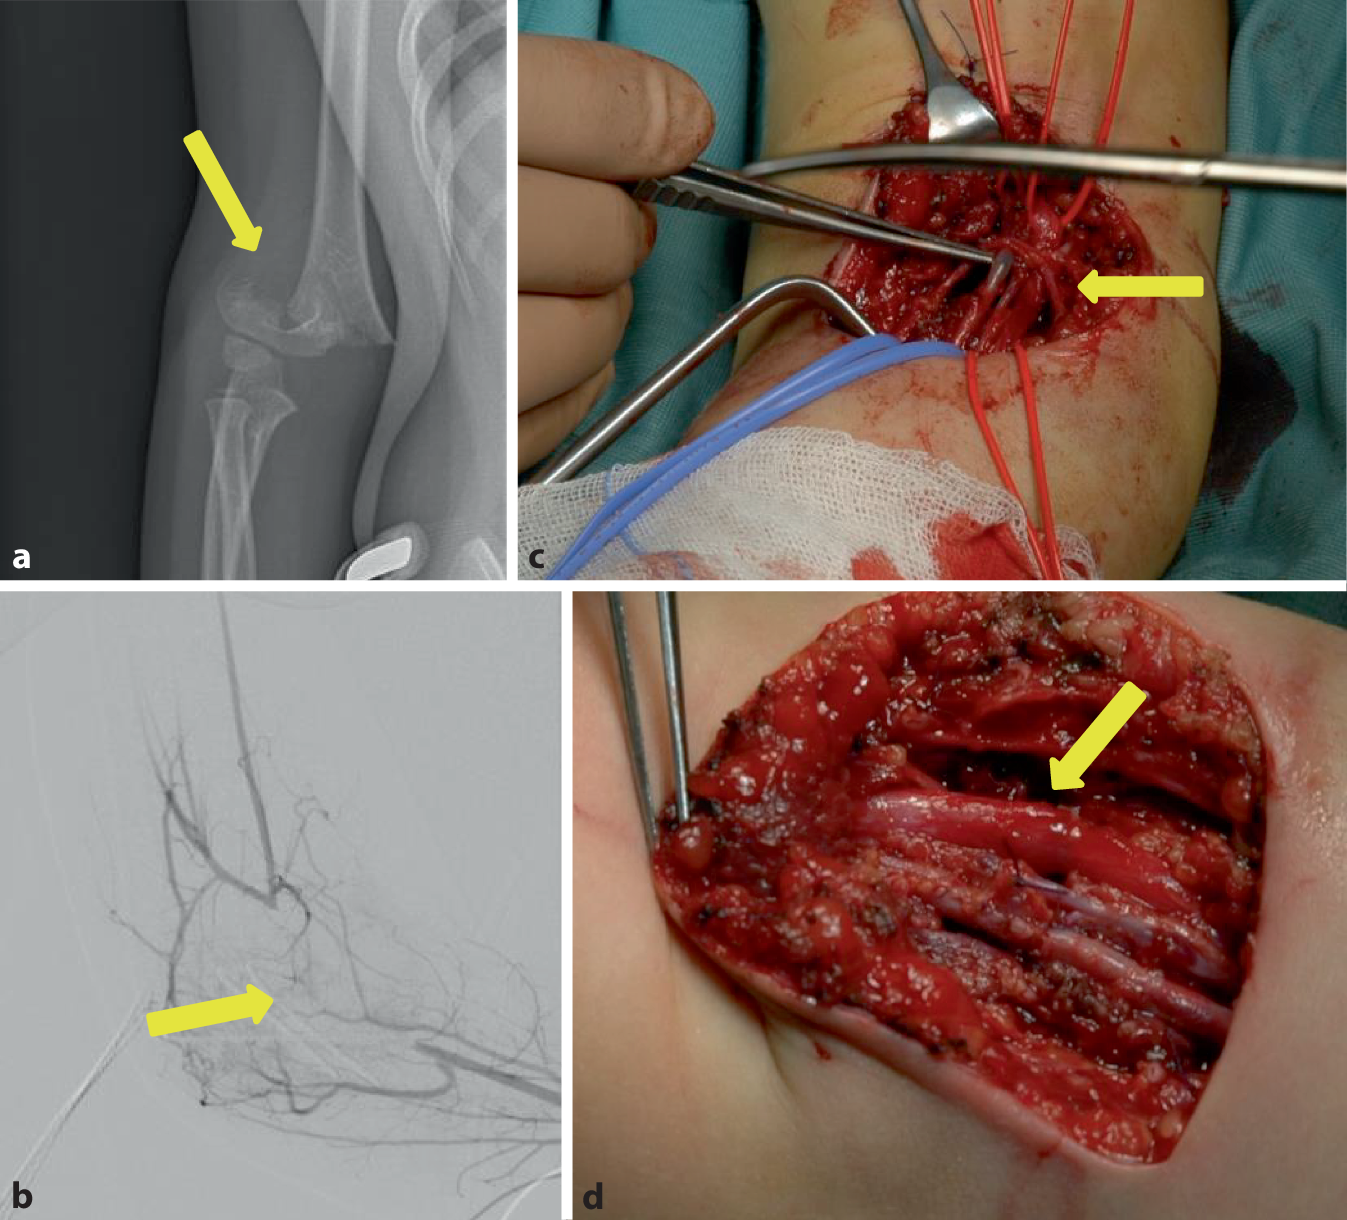

Das dreieinhalbjährige Mädchen hatte sich beim Trampolinspringen eine suprakondyläre Humerusfraktur (Abb. 3a) rechts zugezogen. Nach Erstversorgung in einem auswärtigen Krankenhaus und temporärer Ruhigstellung in einer Armschiene erfolgte die Verlegung des Kindes in die Kinderchirurgie der hiesigen Klinik. Bei der Erstuntersuchung war die Sensibilität bei ängstlichem Verhalten des Kindes nur eingeschränkt beurteilbar, die Motorik schmerzbedingt eingeschränkt. Die Pulse an der A. radialis und ulnaris waren im Vergleich zur Gegenseite abgeschwächt, das kapilläre „Refill“ jedoch erhalten. Es erfolgte zunächst die operative Reposition und Stabilisierung mittels K‑Draht-Osteosynthese. Postoperativ wurde die rechte Hand konsequent pulsoxymetrisch überwacht. Bei einer 100 %igen Sättigung zeigten sich regelhafte Pulskurven. Eine farbkodierte Duplexsonographie der A. radialis und ulnaris zeigte pathologische Flusskurven, sodass anschließend eine DSA durchgeführt wurde (Abb. 3b), die einen Komplettverschluss der A. cubitalis rechts zeigte, der durch Kollateralisierung überbrückt wurde. Daraufhin wurde die Indikation zur operativen Freilegung gestellt. Hier zeigte sich die A. brachialis in den Frakturspalt eingezogen mit einem thrombotischen Verschluss (Abb. 3c). Nach Arteriotomie erfolgte die Thrombektomie und die Patchplastik mit einem Transplantat aus der V. mediana cubiti rechts (Abb. 3d). Nach Beendigung der Patchplastik und Freigabe des Blutstroms konnte ein regelrechtes Doppler-Signal mit der Mikro-Doppler-Sonde abgeleitet werden. Der weitere postoperative Verlauf gestaltete sich komplikationslos bei regelrechter Pulsation von A. radialis und A. ulnaris im Verlauf.

Abb. 3

Fall 3: Thrombose der A. brachialis nach suprakondylärer Humerusfraktur rechts. a Röntgennativbild der suprakondylären Humerusfraktur rechts (anterior/posterior, gelber Pfeil), b digitale Subtraktionsangiographie des rechten Armes mit Nachweis des thrombotischen Verschlusses der A. brachialis rechts (gelber Pfeil), c intraoperatives Bild der thrombosierten A. brachialis rechts (gelber Pfeil), d intraoperatives Bild der rekonstruierten A. brachialis rechts (gelber Pfeil)